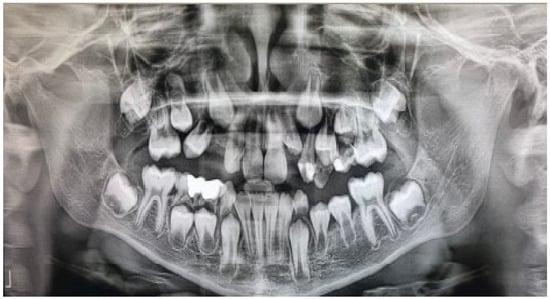

The same procedure was performed as in the first case, in which the first and second upper and lower deciduous molars were extracted. A biopsy was taken at both sites, and the same decompression devices were placed in the extraction sockets. The patient was advised to irrigate the cyst cavities with saline [Figure 6]. Histopathologic analysis of the lesions confirmed the diagnosis of dentigerous cysts, characterized by lining of 2–4 layers of non-keratinized epithelium and infiltration of inflammatory cells within the fibrous wall. Postoperative radiographs showed a gradual reduction of the lesions, and all permanent teeth erupted after one year [Figure 7]. No recurrence of the lesions was noted on a three-year follow-up radiograph [Figure 8]. The patient was referred to an orthodontist for the correction of occlusion.

Figure 7. Twelve-month postoperative panoramic radiograph showing the resolution of both lesions.

Figure 8. A three-year follow-up panoramic radiograph showing no recurrence of the lesions.